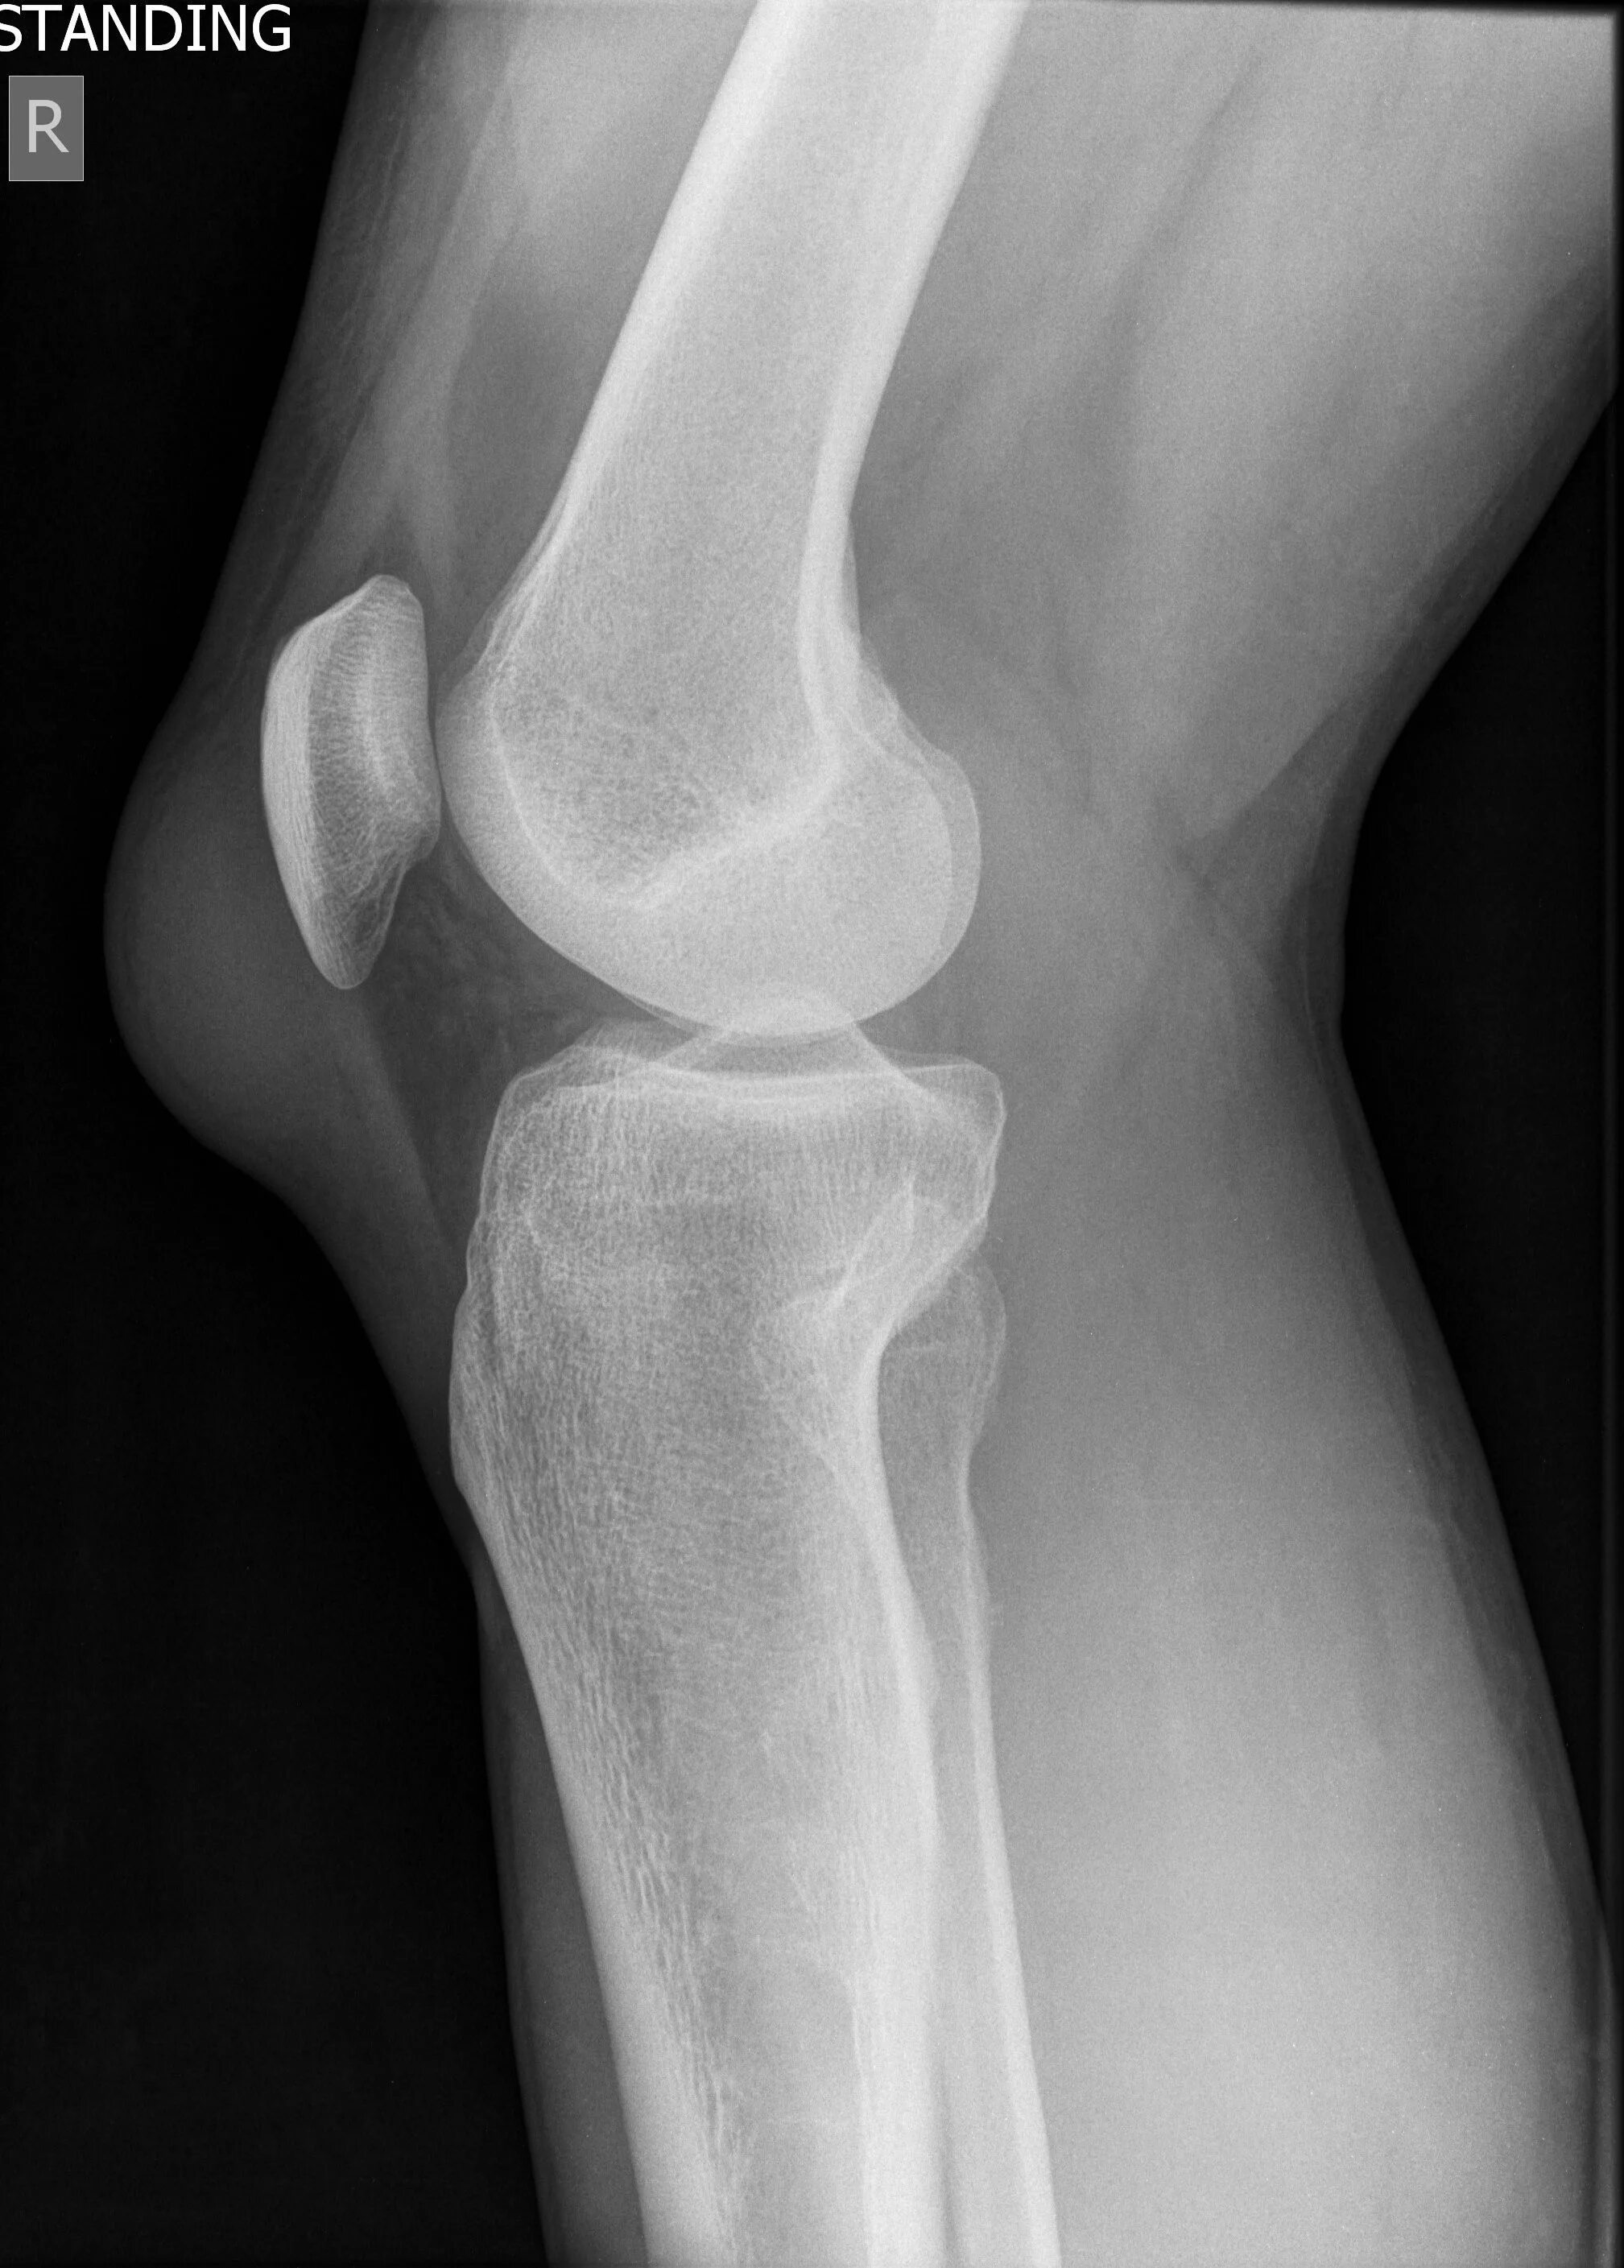

Синдром осгуда шляттера